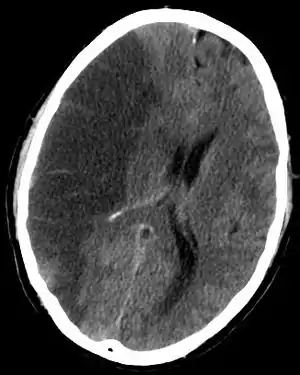

| CT scan slice of the brain showing a right-hemispheric cerebral infarct (left side of image). | |